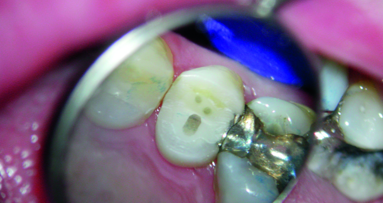

A 64-year-old female presented to the endodontic office with an uneventful medical history. She complained of spontaneous pain on the lower left side of one week’s duration, which radiated up the ramus of the jaw and was causing headaches. She also complained of hot and cold sensitivity with pain on biting. Clinical tests revealed pain to cold, which lingered for five minutes and a sharp electric like pain when a tooth sleuth was placed over the DL cusp tip. A distal crack was visualised. There was no periodontal pocketing. All other mandibular left and maxillary left teeth tested vital and asymptomatic. The radiograph revealed a small shallow minimally invasive amalgam restoration (Fig. 3). The diagnosis was Cracked Tooth Syndrome with an irreversibly inflamed pulp. The patient was advised of the questionable long term prognosis with cracked teeth yet decided to try and retain it understanding that if the crack extends in the root proper and a periodontal pocket develops, then extraction with an implant replacement may be a viable solution.

Due to the minimal invasiveness of the restoration, it is anticipated that after endodontic treatment, there would be enough coronal tooth structure left to allow for the preparation of a full coverage restoration with a fully circumferential ferrule of at least 2+mm in height, as well as width (Fig. 4). Figure 5 is a magnified view of the distal vertical crack, with the wear facet on the lingual cusp indicating a working side contact interference. Endo dontic therapy was initiated under the microscope and after a thorough debridement and shaping of the root canal spaces (Fig. 6), the roots were obturated with gutta percha using a continuous wave of condensation technique to a level 2mm below the pulpal floor (Fig. 7). Phosphoric acid etching was initiated with the placement of Ultra-Etch Etchant (Ultradent) followed by microbrush agitation to work the etchant into the dentine, a thorough rinse, and light air drying (Fig. 8). Figure 9 shows the application of MPa bonding agent (Clinical Research Dental) with a microbrush, which again was followed by agitation to facilitate deeper penetration of the bonding agent, followed by evaporation of the solvent for ten seconds. The bonding agent was cured with a Valo Curing Light (Ultradent) for ten seconds utilising a Valo Proxiball Lens (Fig. 10). The Macro-Lock X-RO segments are verified for fit over the three canal orifices, and then coated with MPa bonding agent, which was cured for ten seconds (Fig. 11). Cosmecore (Cosmedent) A2 is injected into the pulp chamber one half way up the occlusal height of the clinical crown (Fig. 12). The Macro-Lock X-RO segments are inserted into the Cosmecore followed by a 10 second cure with the Valo (Fig. 13). The rest of the occlusal access opening is filled with the Cosmecore and thoroughly cured with the Valo for 20 seconds. Figure 14 is the final post-operative radio graph showing the placement of the fibre segments into the core. The final restoration of the occlusal access opening is shown in Figure 15 after trimming and occlusal adjustment. The endodontically treated tooth is now ready for a final restoration.